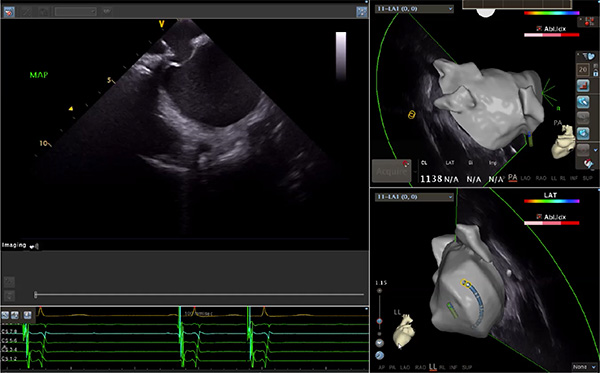

超聲心動圖技術(shù)包括常規(guī)經(jīng)胸超聲(TTE)、經(jīng)食管超聲(TEE)、心腔內(nèi)超聲(ICE)、超聲聲學(xué)造影(MCE)、三維超聲心動圖等,ICE是一種新興技術(shù)——將微型的換能器安裝在心導(dǎo)管的尖端,經(jīng)由外周血管輸送至心腔內(nèi)部,換能器發(fā)射聲波,對心臟及其鄰近組織進(jìn)行實時高質(zhì)量成像和(或)血流動力學(xué)測定的超聲成像技術(shù)。基于不同的技術(shù)原理,心腔內(nèi)超聲導(dǎo)管被分為兩類:機(jī)械旋轉(zhuǎn)式超聲導(dǎo)管和相控陣超聲導(dǎo)管。目前,臨床上主要應(yīng)用的是相控陣超聲導(dǎo)管,ICE成像通過術(shù)者旋轉(zhuǎn)導(dǎo)管及操縱導(dǎo)管手柄上的兩個旋鈕來完成。

ICE門檻高、集成了超聲和圖像處理最前端的技術(shù),是當(dāng)前內(nèi)窺超聲方向最挑戰(zhàn)的領(lǐng)域。不同于傳統(tǒng)接觸式三維重建方法會產(chǎn)生假腔,影響術(shù)者對靶點或結(jié)構(gòu)的判斷,心腔內(nèi)超聲(ICE)可直接顯示心臟結(jié)構(gòu),有助于理解心臟內(nèi)各部位之間的解剖關(guān)系,不僅具有實時成像、并發(fā)癥監(jiān)測以及良好的耐受性,同時以股靜脈入路,無需全麻或深度鎮(zhèn)靜,日益成為心臟介入手術(shù)中重要輔助工具,被譽(yù)為心臟介入醫(yī)生的“黃金眼”。心腔內(nèi)超聲可用于多種心臟介入手術(shù),潛在患者群體龐大,動脈網(wǎng)測算我國心腔內(nèi)超聲導(dǎo)管市場空間或?qū)⒊?00億元,具有廣闊前景。

隨著心腔內(nèi)超聲的應(yīng)用更廣,性能也在逐漸優(yōu)化,已從二維成像轉(zhuǎn)變?yōu)?strong>三維成像,極大增強(qiáng)了引導(dǎo)及可視化能力。二維心腔內(nèi)超聲支持雙平面或三平面成像,可顯示兩個或三個不同的平面視圖,但醫(yī)生需將這些圖像在腦海中重新構(gòu)建為三維解剖結(jié)構(gòu)。三維心腔內(nèi)超聲則可直接呈現(xiàn)三維解剖結(jié)構(gòu)圖,便于醫(yī)生更輕松地開展手術(shù)。按照產(chǎn)品發(fā)展方向,預(yù)計心腔內(nèi)超聲還將向更清晰、精準(zhǔn)、多功能等方向發(fā)展。